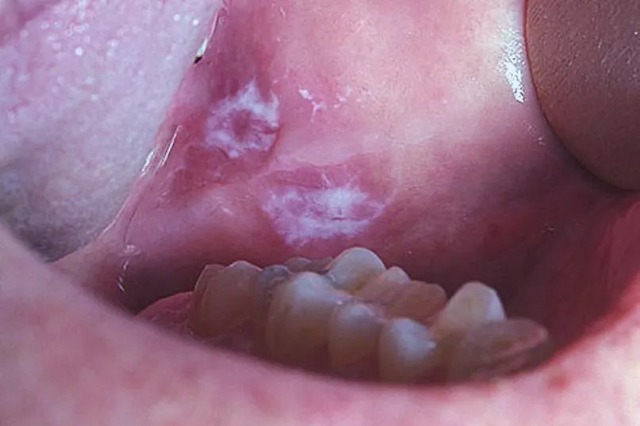

Trước khi phát triển thành vết nhiệt miệng rõ ràng, ung thư khoang miệng có thể bắt đầu bằng các tổn thương tiền ung thư (tiền ác tính) dưới dạng mảng màu bất thường, thường bị nhầm lẫn với nấm hoặc đổi màu niêm mạc.

Cụ thể là các mảng trắng (Leukoplakia) có màu trắng xám, dày, thường không gây đau, hoặc các mảng đỏ (Erythroplakia) có màu đỏ tươi, nhung. Nếu bạn nhận thấy bất kỳ mảng trắng hoặc mảng đỏ nào không thể cạo đi được và không biến mất trong vòng 2 tuần, cần phải đi kiểm tra ngay lập tức. Đây là dấu hiệu cảnh báo sớm nhất của sự phát triển tế bào ác tính.